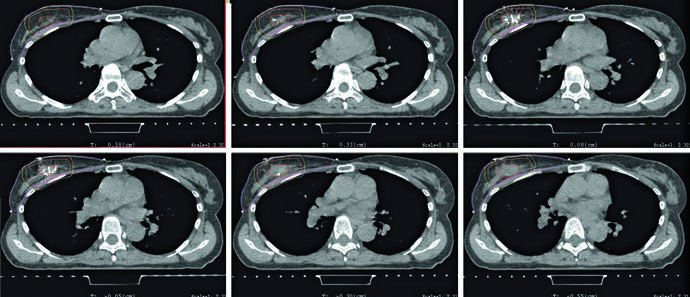

As figuras de planejamento deixam esse raciocínio concreto. O exemplo supino mostra tangentes com field-in-field para homogeneidade e um pequeno bloqueio por MLC para proteção cardíaca. Na mesma legenda, a prescrição aparece de forma direta: 42,4 Gy em frações de 2,65 Gy, seguidos de boost com elétrons na cavidade da lumpectomia até 10 Gy em frações de 2,5 Gy. O capítulo, portanto, não trata a compensação como um refinamento opcional. Ela já integra a técnica padrão desde o início do plano.

Essa comparação entre supino e prono conversa diretamente com o planejamento das figuras. O exemplo em prono usa tangentes com field-in-field, a mesma prescrição de 42,4 Gy em 2,65 Gy por fração e boost com mini-tangentes fotônicos até 10 Gy em 2,5 Gy por fração. A legenda ainda acrescenta um detalhe anatômico que serve de guia: a borda posterior do campo deve incluir parte do músculo peitoral. Para quem quiser avançar do raciocínio da mama inicial para cobertura regional, vale continuar a leitura no nosso artigo sobre irradiação nodal regional no câncer de mama.

As figuras do capítulo não servem apenas para ilustrar o texto; elas refinam a tomada de decisão. As imagens axiais em supino e prono mostram como a relação entre mama, pulmão e coração muda com o setup, e isso explica por que o capítulo não trata a posição da paciente como questão de preferência pessoal. A figura de APBI, por sua vez, aproxima a regra abstrata da expansão do que realmente se vê na tomografia, deixando claro onde o CTV deve parar e onde o PTV pode ultrapassar a superfície.